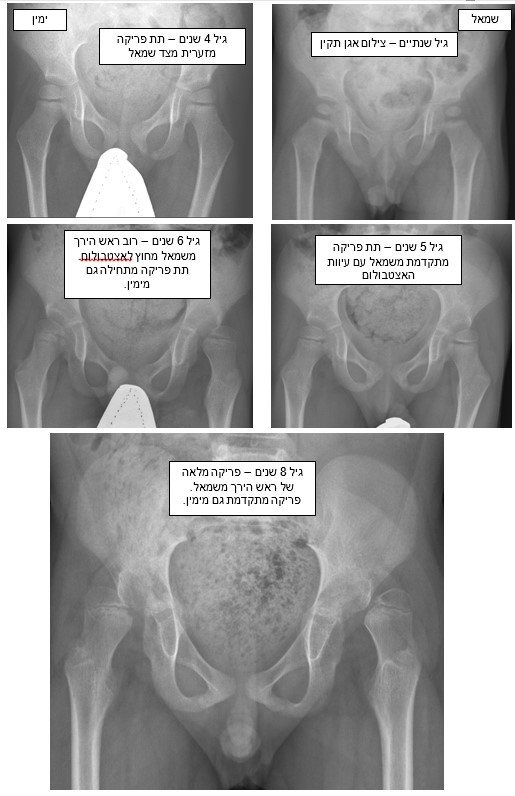

בסדרת הצילומים להלן נראית פריקה מתקדמת של מפרקי הירך בילד עם שיתוק מוחין בדרגת תפקוד GMFCS 4.

הצילומים בוצעו בגילים: 2, 4, 5, 6, והאחרון בגיל 8 שנים.

(ההסתכלות על צילומים נעשית כאלו הילד עומד מולנו).